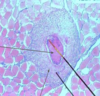

Toxoplasma - Tachyzoites

Stained with immunofluorescent method

Toxoplasma

Tachyzoites

Toxoplasma Gondii

Tachyzoites

Giemsa staining